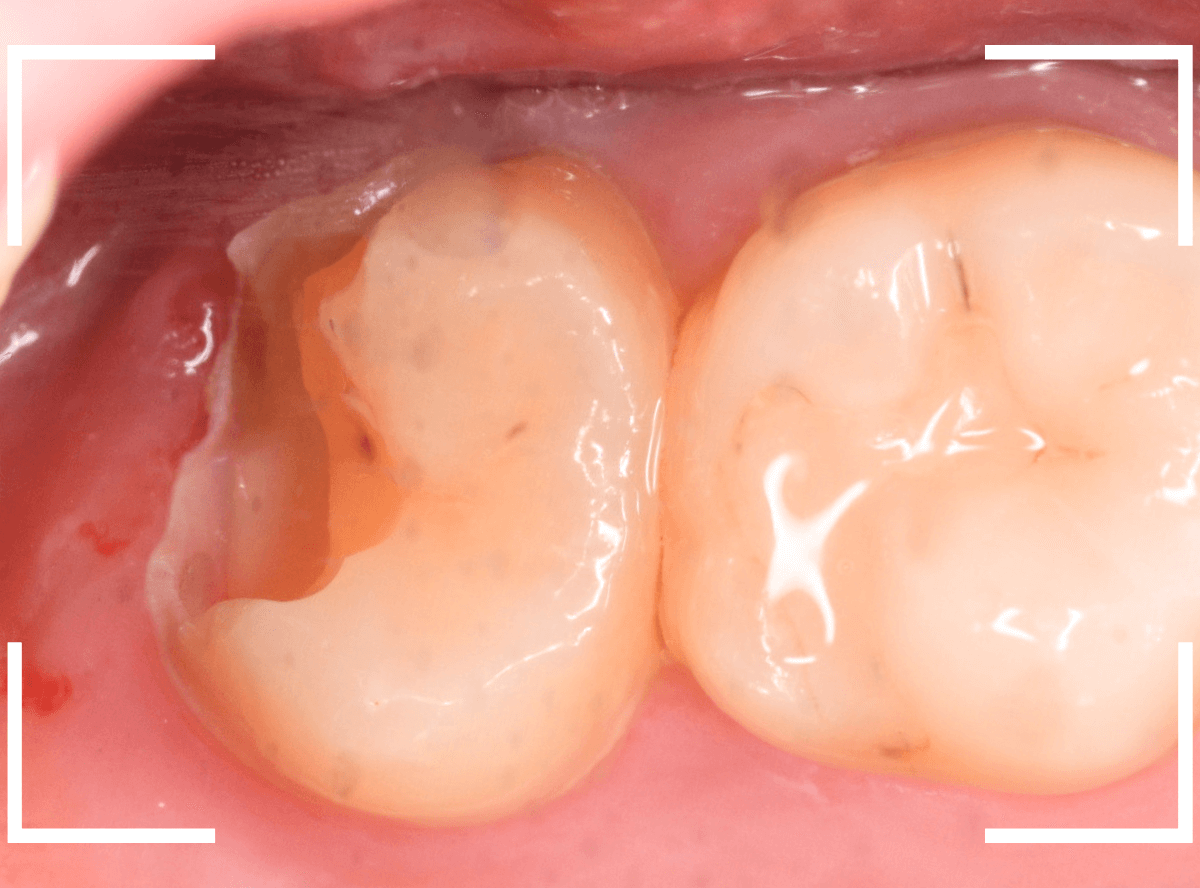

上の奥歯が痛むという訴えで来院された患者さんです。

一番奥の歯(左)が虫歯になっているのが一目でわかります。

虫歯も深そうです。

治療を開始します。

赤く染まっている部分が虫歯です。

思った通り、かなり深く進行していますね。

奥歯の虫歯が全部除去できましたので、手前の歯の虫歯も治療します。

全ての虫歯を除去しました。

レントゲンから予測した通り、かなり広範な虫歯でした。